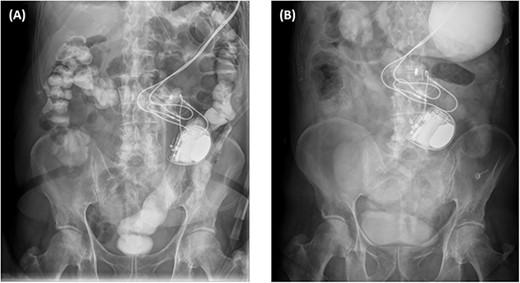

The abdominal computed tomography (CT) studies on all three recent admissions were consistent with SBO. The transition point was consistently seen in the right iliac fossa; with small bowel loops distended proximally with air-fluid levels and faecalised contents; and small bowel loops collapsed distally to the ileocaecal valve (Fig. 1A). There were no signs of bowel ischaemia or perforation. However, the preperitoneal ICD appeared to have migrated into the peritoneal cavity (Fig. 1B). On review of the serial abdominal CT studies over the past two years, the ICD was in a different intraperitoneal location each time (Fig. 2). The recurrent episodes of SBOs were thus believed to be related to the ICD, due to either intraperitoneal migration of the device or formation of adhesions from its placement, given the coinciding timeline.

Axial computed tomography images showing small bowel obstruction with a transition point in the anterior right iliac fossa (cross). There are distended small bowel loops proximally with air-fluid levels and faecalised contents (arrows); and collapsed small bowel loops distally (arrow heads). The ICD is located intraperitoneally (star).